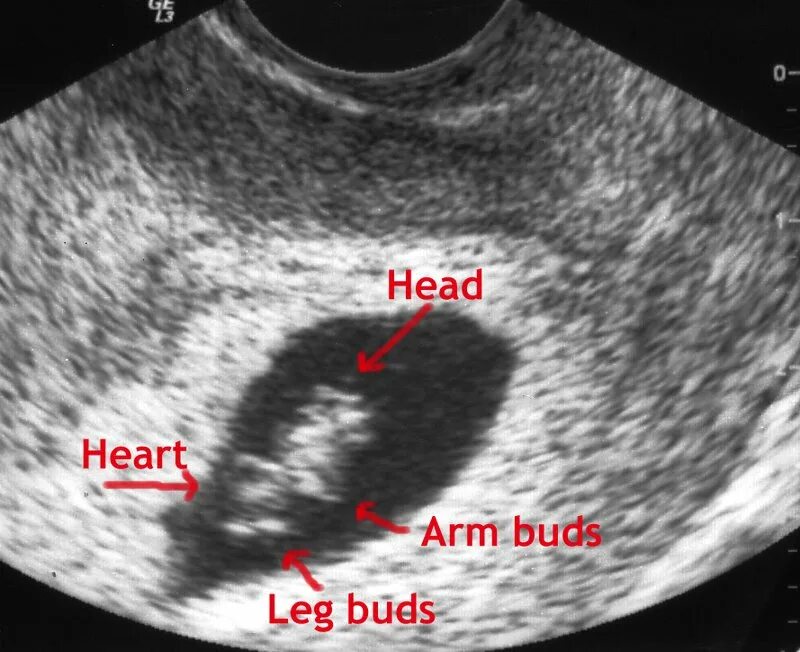

7 недель ощущения